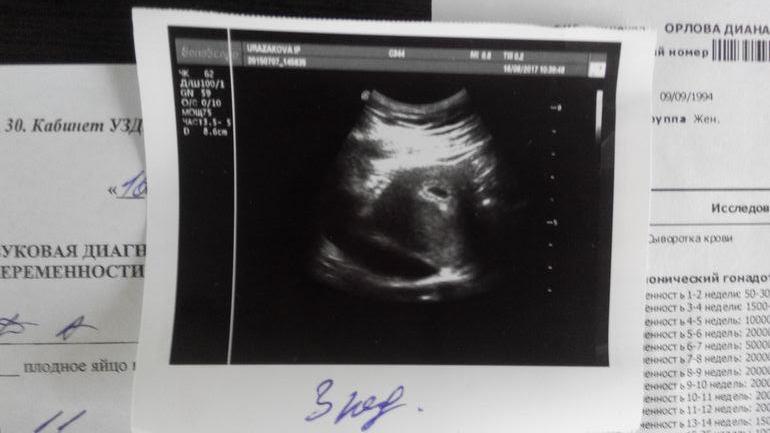

Уже более 1000 должен быть и тест хорошо полосатились,так что можешь идти на УЗИ и проверить плодное яйцо должно уже быть видно,у меня на 7 ой день задержки было уже видно вот так,

0